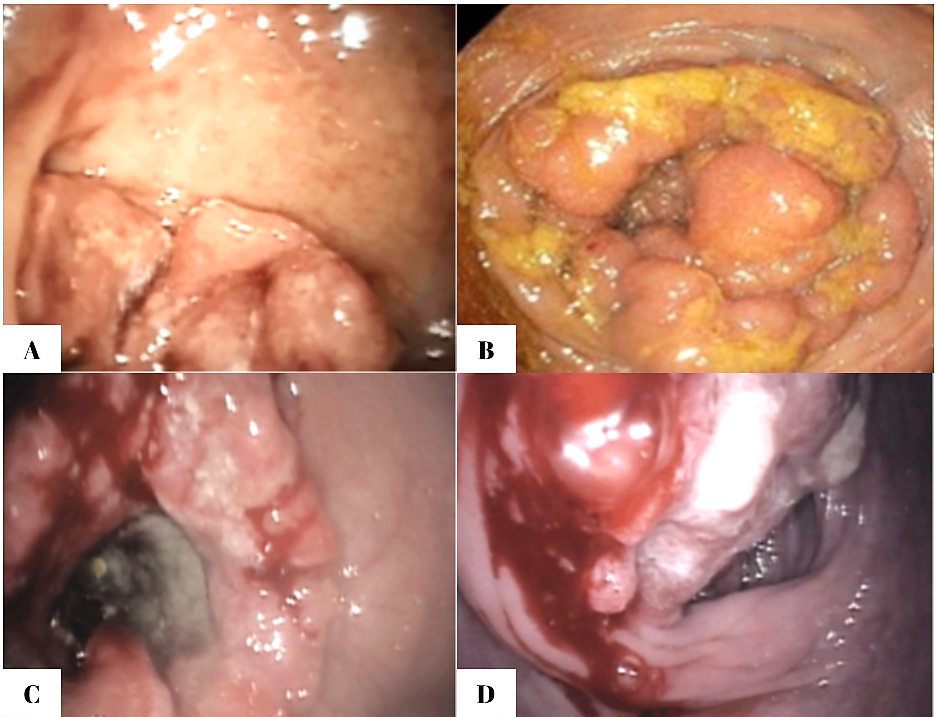

Regarding the endoscopic aspect, colorectal neoplasm presented in the following forms: vegetative formations accounted for 54.6% (n=42) of the 77 patients, vegetative-ulcerative tumor formations were observed in 24.6% (n=19), infiltrative formations with areas of ulceration were described endoscopically in 10.4% (n=8), while the classic infiltrative tumor aspect was detected in 8 patients (10.4%), as summarized in Figure 1.

|

Fig. 1 Endoscopic appearance of colonic neoplasia in patients included in the study |

Figure 2 shows endoscopic images that reflect the appearance of different forms of colorectal tumors, all of which require histopathological confirmation. The ulcerated type, the most common, appears as a circular mass with a raised, irregular, and externalized border. It is frequently large, occupying an extensive portion of the colonic circumference. The polypoid form presents as a large mass protruding into the lumen. In 10% of cases, it has a mucinous structure characteristic of colloid carcinoma. The annular or stenotic form occupies the entire colonic lumen, with variable extension along the longitudinal axis of the colon.

|

Fig. 2. Endoscopic images of colorectal tumors A – vegetative formation; B – circumferential stenosing vegetative formation, impassable with the colonoscope; C – ulcer-infiltrative formation; D – vegetative formation covered by areas of necrosis |